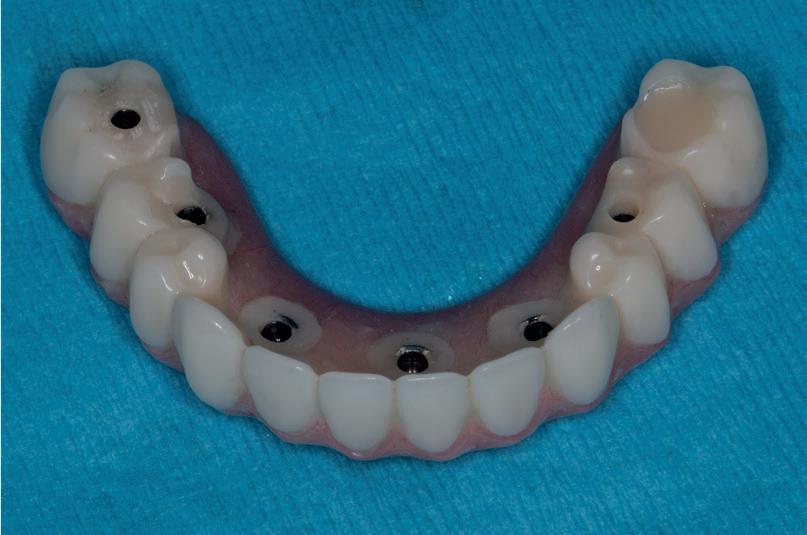

REABILITAREA implanturilor în zona estetică. Acest articol detaliază două cazuri rezolvate prin tehnica extracției parțiale, finalizate fără grefarea compartimentului dintre implant și scut, și monitorizate cinci ani, dovedind stabilitatea volumetrică a țesuturilor moi și dure în timp.